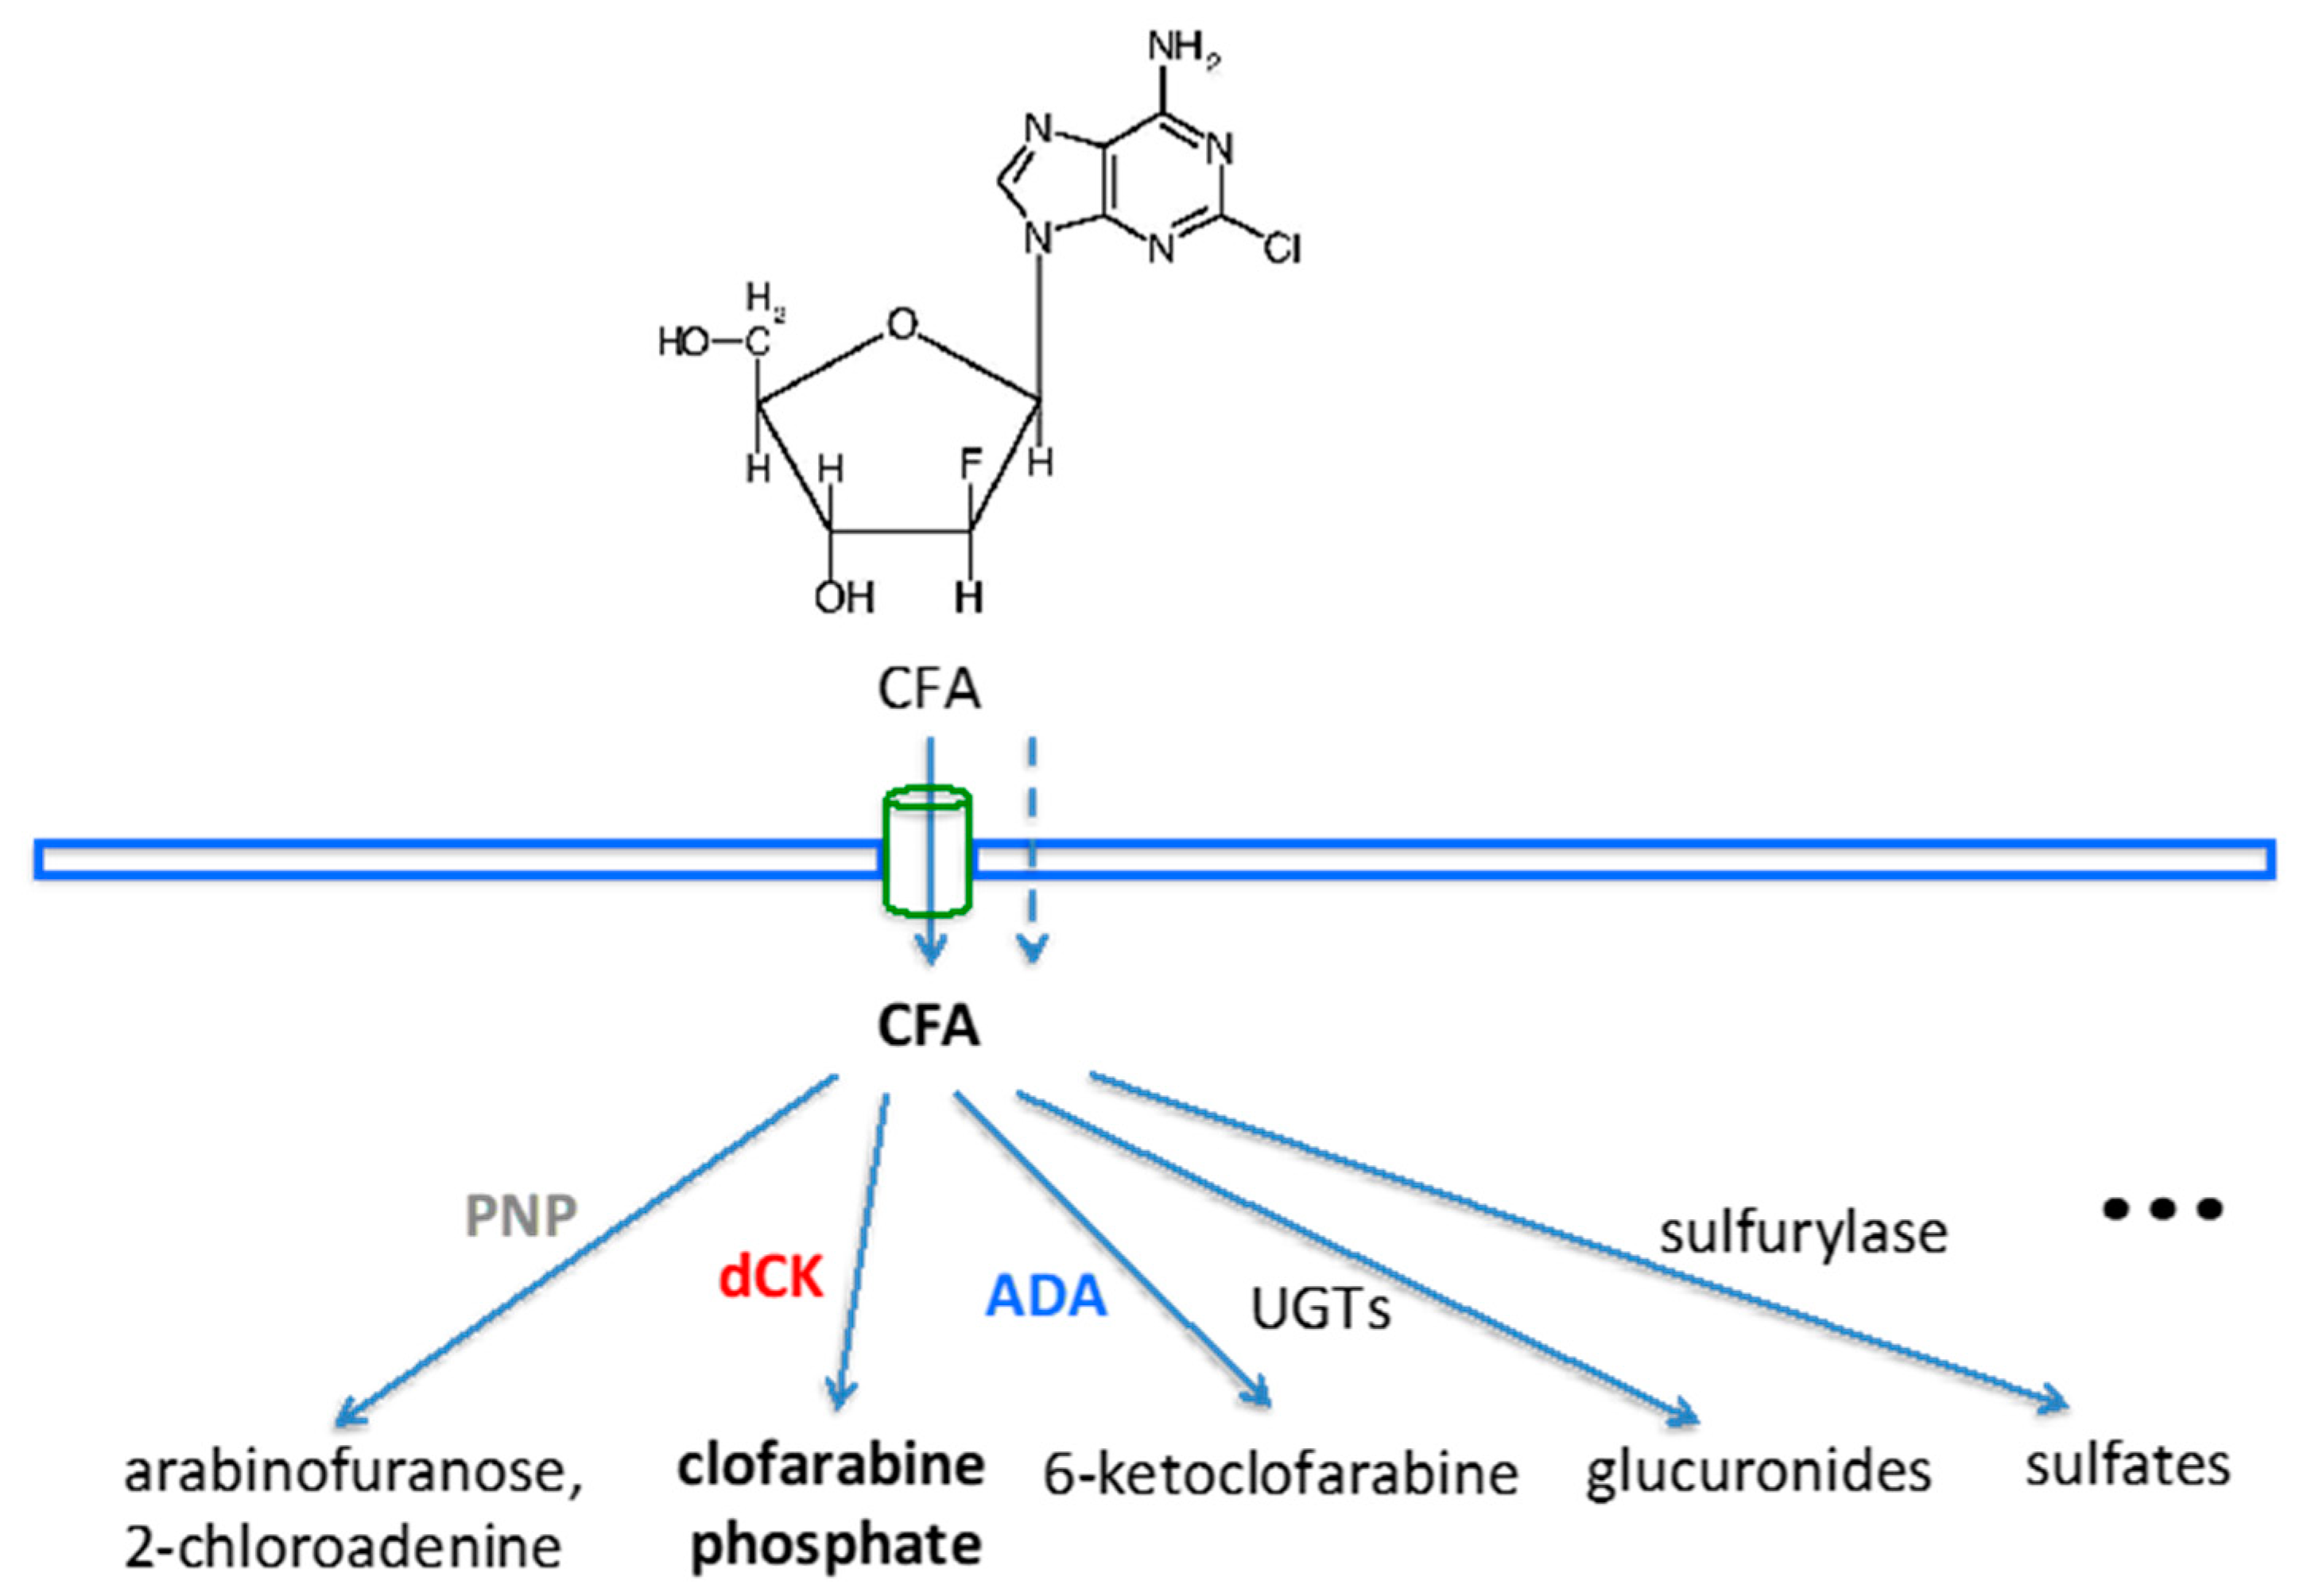

1. Introduction

2. Results

2.2. PET Imaging